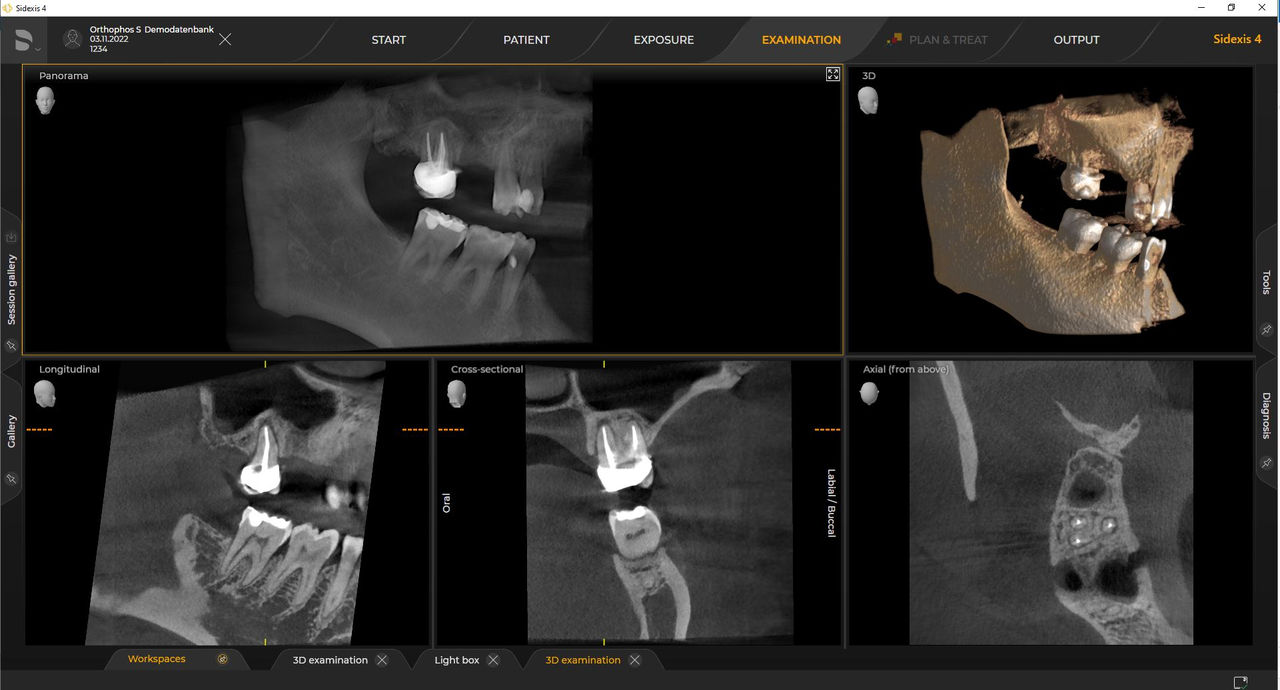

Las unidades de radiología de Dentsply Sirona funcionan exclusivamente con Sidexis 4. Sin embargo, la migración de datos de Sidexis XG a Sidexis 4 es muy fácil. Sidexis 4 permite una experiencia digital completa con las últimas herramientas

Orthophos S de 2D permite una actualización 3D. Axeos es una unidad híbrida exclusiva. El Orthophos E no ofrece esta opción.